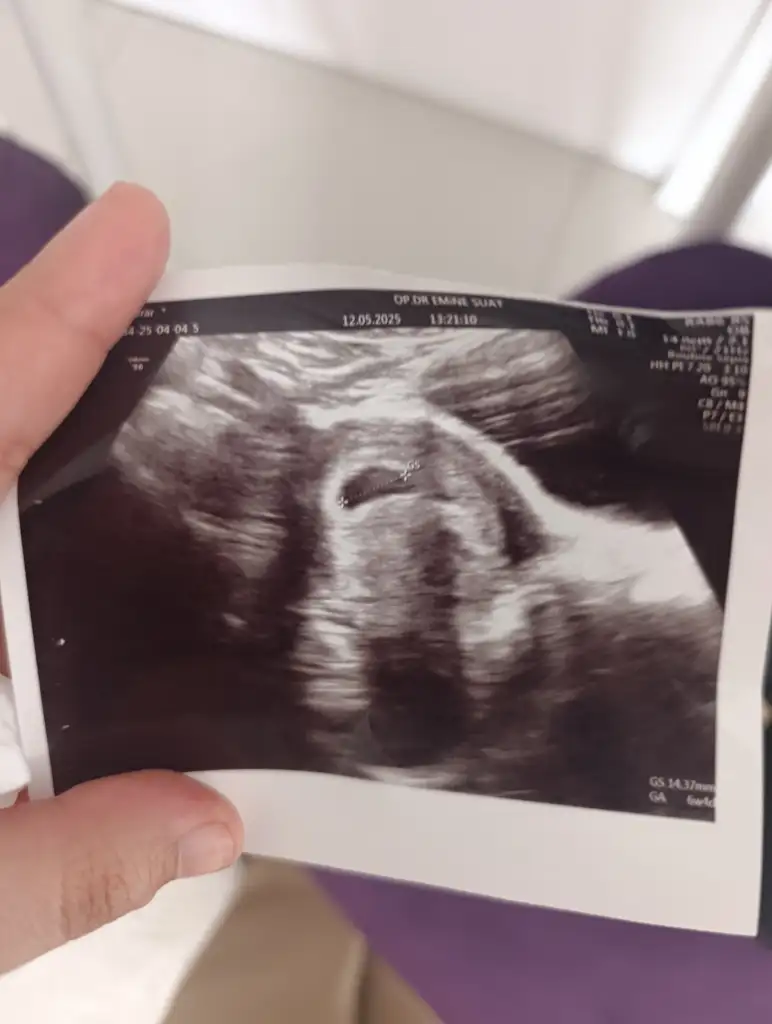

Ay inşallah bi sorun yokturAşkooooo keseye göre kız gibi ama normal duruyor benim kesem baya büyük oval

Kız benimkinwde bak biiAşkooooo keseye göre kız gibi ama normal duruyor benim kesem baya büyük oval

Erkek kesesi gibiKız benimkinwde bak biiEki Görüntüle 3591378

Erkek de oval kız da yuvarlak oluyor genedleKızda naskl oluyor erkekte nasıl oluyor

Erkek de oval kız da yuvarlak oluyor genedle